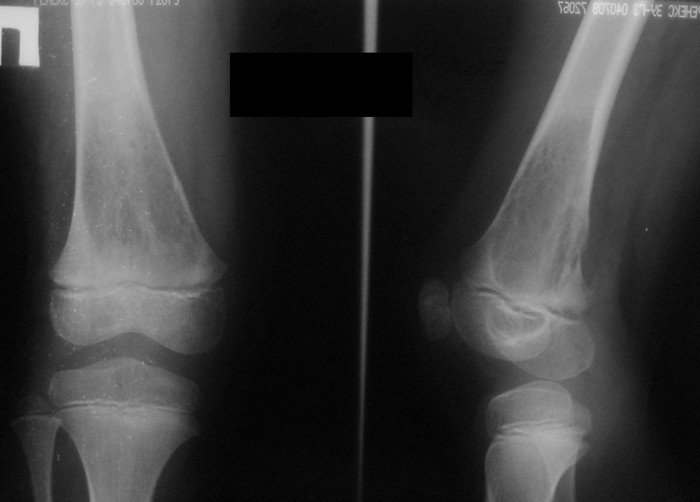

3 месяца назад в отделении была прооперирована девочка 7 лет с клинико- рентгенологической картиной аневризмальной кисты (открытая биопсия). Гистологическое заключение местных гистологов и ФНКЦ им. Д. Рогачева -аневризмальная киста. 2 недели назад девочка взята на костную пластику - на операции полный лизис костной ткани циркулярно на протяжении 10 см от эпифиза на 10 проксимальней и массивное артериовенозное крововтечение из оставшейся надкостницы . Операция закончена наложением стержневого аппарата и остановкой кровотечения тахокомбом, тампонадой мышцами. Повторная гистология неоднозначна. ФНКЦ им. Д. Рогачева дает прежний результат , ФГБУ РОНЦ НН Блохина -телеангиэктатическая остеосаркома, онкологи из института Герцена - киста .Как быть дальше. Кому верить и что делать? Заранее благодарен.

Судя по рентгенам и КТ, больше похоже на саркому, так как границы опухоли размыты. Аневризмальная киста обычно находится не по центру кости, а с одного края. Результаты гистологии надо всегда смотреть вместе с рентгенами. Если в каких-то из трёх центров видели только гистологию, то имеет смысл попросить их посмотреть и рентгены с КТ. Ежели всё видели и заключение не меняется, то можно попробовать послать в какой-нибудь очень крупный онкологический центр вроде Instituto Ortopedic Rizzoli в Италии или Mayo Clinic в США.